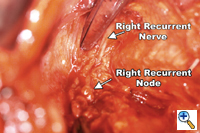

Dissection of the "third-field" begins during the thoracic portion of the procedure and is later completed through a collar neck incision. Dissection of the nodes in the superior mediastinum includes the nodes along the right and left recurrent laryngeal nerves throughout their mediastinal course. The paratracheal retrocaval compartment is not disturbed. The left recurrent nerve is dissected using a "no-touch" technique and nodes along its anterior aspect are carefully excised (Figure 3). Notably, there is a paucity of nodal tissue along the left nerve in nearly all Caucasians. The right recurrent nerve is carefully exposed near its origin at the base of the right subclavian artery. The right recurrent nodal chain begins at that level and forms a continuous package that extends through the thoracic inlet to the neck. Again, the nerve is dissected using a strict "no-touch" technique (Figure 4). Through the cervical incision, the remainder of the recurrent nodes are dissected as are the lower deep cervical nodes located posterior and lateral to the carotid sheath. Thus the "third-field" includes a continuous anatomically inseparable chain of nodes that extends from the superior mediastinum to the lower neck. These nodes should be appropriately labeled cervicothoracic (CT) nodes rather than cervical nodes.

A generous low collar incision is performed and subplatysmal flaps are raised inferiorly and superiorly. The strap muscles and the medial heads of the sternocleidomastoid are divided. The esophagus (previously fully mobilized from the thorax) is retrieved from the prevertebral space. The esophagus is divided distally and the specimen is retrieved in the abdomen. The previously dissected recurrent nerves are easy to visualize (especially the right recurrent) and any residual nodal tissue is excised (Figure 6). Next, the nodes posterior and lateral to the carotid sheath are removed along with the supraclavicular nodes (Figure 7). The dissection is limited superiorly by the inferior belly of the omohyoid. Within the abdomen the gastric tube is prepared and the specimen is removed (Figure 8). Gastrointestinal continuity is restored by a cervical esophagogastrostomy.

- Never directly handle or encircle the recurrent nerves with a vessel loop for retraction purposes. A "no-touch" technique is essential to reduce the probability of recurrent nerve injury. In my experience, the incidence of recurrent nerve injury is 5-10%. No patient has required a tracheostomy for recurrent nerve injury.

- The right vagus nerve serves as a good guide to locate the right recurrent nerve. Attempts to directly locate the nerve are potentially hazardous.

- During the cervical portion of the operation, be particularly careful in identifying the recurrent nerves. Deprived of their supporting areolar tissues, the nerves tend to "wander" out of the tracheoesophageal groove.